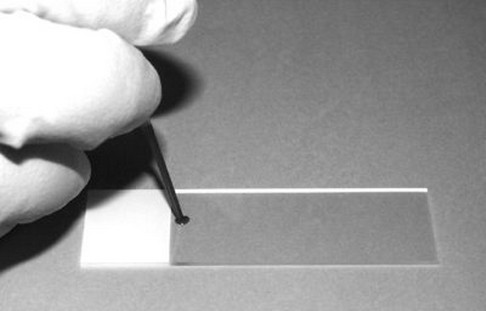

Onderstaande tekening geeft aan hoe een druppel bloed uitgestreken wordt op een objectglaasje. Belangrijk is dat het bloed door het tweede objectglaasje wordt meegetrokken en dus niet voortgeduwd, anders zouden alle bloedcellen kapot gedrukt worden. Het voortbewegen van het glas moet vrij snel gebeuren maar vooral met een éénparige snelheid. Zo kan een dunne laag worden verkregen. De beste plekken om te bekijken zijn de randen en de vlag (laatste deel van de uitstrijk).

De procedure nogmaals in beeld,

![]() | Druppel bloed aanbrengen. |

![]() | Tweede objectglas aanbrengen en langzaam tegen de druppel aanschuiven. |

![]() | Druppel tot aan rand laten uitvloeien. |

![]() | De druppel met een éénparige beweging uitstrijken. |

![]() | Tot aan de rand doorgaan met uitsmeren. |

![]() | Preparaat een uur aan buitenlucht laten drogen. |